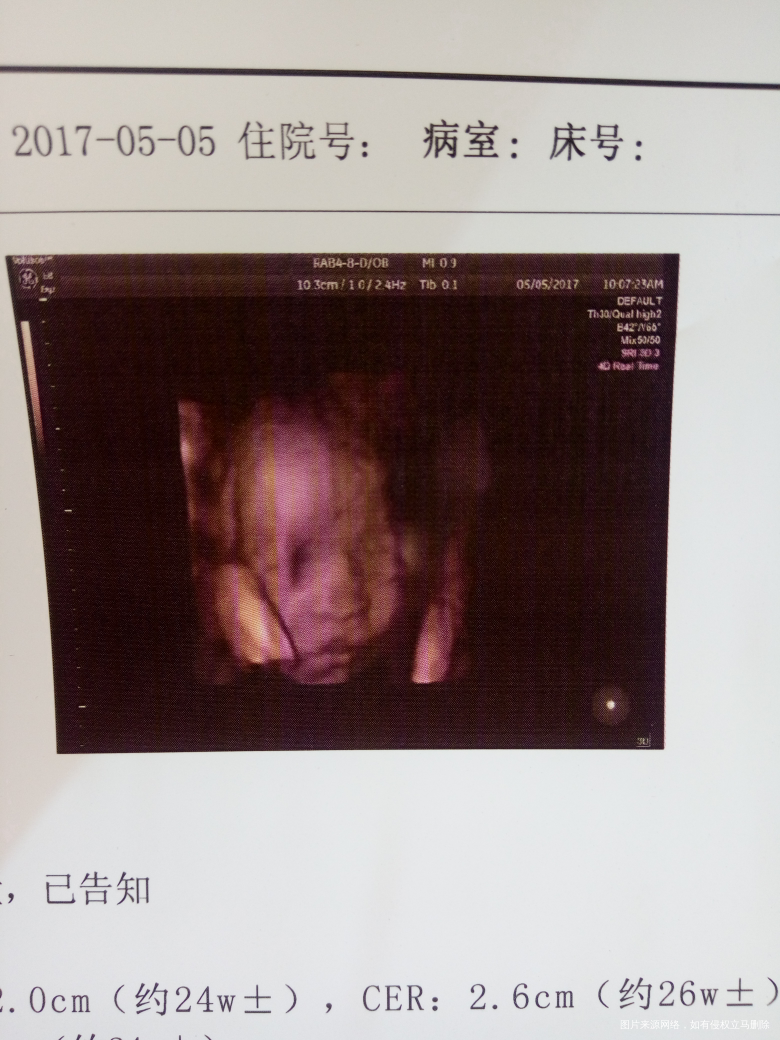

非常谢谢你愿意做我的宝贝,在你16周的时候能感觉你在里面动那是真实的感觉你的存在,幸福感满满的给你爸爸说你爸爸把耳朵贴在妈妈的肚皮上要感觉你的胎动,你爸爸好傻现在怎么试出你在里面动那,听别人说胎儿五个月就能听到外面的声音所以妈妈想给你取个乳名也不知道你是男是女,我跟你爸爸都希望你是个女孩所以给你取了个女孩的名字叫小米,虽然你爸爸不同意我还是天天叫你小米[大笑],昨天去做四维彩超医生说我肚皮厚看的不是很清楚,医生让我看屏幕说看看孩子的小模样,看你第一眼的时候我被你的模样暖化的,都说自己的孩子越看越可爱真的我都不舍得挪开眼睛

回来给你奶奶看你奶奶足足看了半个多小时,发照片给你姥爷姥姥都说你脸大嘴也大,[大笑]医生说你很健康,宝宝非常感谢你愿意来到我的身边全家人都很期待你的到来,现在妈妈都能想象出我和你爸爸大手拉着你的小手陪你快乐的成长